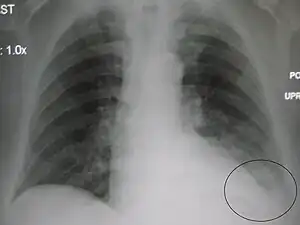

In anatomy, the costophrenic angles are the places where the diaphragm (-phrenic) meets the ribs (costo-).

Each costophrenic angle can normally be seen as on chest x-ray as a sharply-pointed, downward indentation (dark) between each hemi-diaphragm (white) and the adjacent chest wall (white). A small portion of each lung normally reaches into the costophrenic angle. The normal angle usually measures thirty degrees.

Pleural effusion

With pleural effusion, fluid often builds up in the costophrenic angle (due to gravity). This can push the lung upwards, resulting in "blunting" of the costophrenic angle. The posterior angle is the deepest. Obtuse angulation is sign of disease.

Chest x-ray is the first test done to confirm the presence of pleural fluid. The lateral upright chest x-ray should be examined when a pleural effusion is suspected. In an upright x-ray, 75 mL of fluid blunts the posterior costophrenic angle. Blunting of the lateral costophrenic angle usually requires about 175 mL but may take as much as 500 mL. Larger pleural effusions opacify portions of the hemithorax and may cause mediastinal shift; effusions > 4 L may cause complete opacification of the hemithorax and mediastinal shift to the contralateral side.